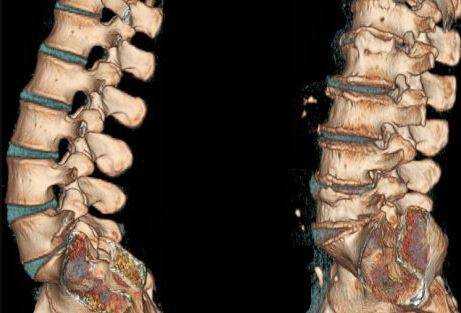

Метод КТ пояснично-крестцового отдела позвоночника основан на работе рентгеновских лучей, однако, используя томограф, врач получает серию послойных снимков и объемное изображение, на которых четко видны нарушения конфигурации и структуры сканируемого органа. Такой метод называется - мультиспиральная компьютерная томография пояснично-крестцового отдела (МСКТ).

КТ поясничного отдела позвоночника что покажет

Фотографии, получаемые в результате процедуры, и 3D-модель дают четкое представление о состоянии поясничных и крестцовых позвонков, помогают оценить строение костной и хрящевой ткани, ширину позвоночного канала, структуру нервных волокон корешков спинного мозга. КТ пояснично-крестцового отдела показывает толщину межпозвонковых дисков, их сохранность, функциональность.

Благодаря послойному сканированию на фото хорошо видны малейшие нарушения формы позвонка, его целостности, наличие патологических пустот в костной ткани и новообразований различного характера. Чем плотнее структура ткани, тем ярче она будет выглядеть на снимке. Поэтому самыми светлыми являются очертания костей и хрящей, рыхлые элементы и участки деструкции выглядят темными пятнами.